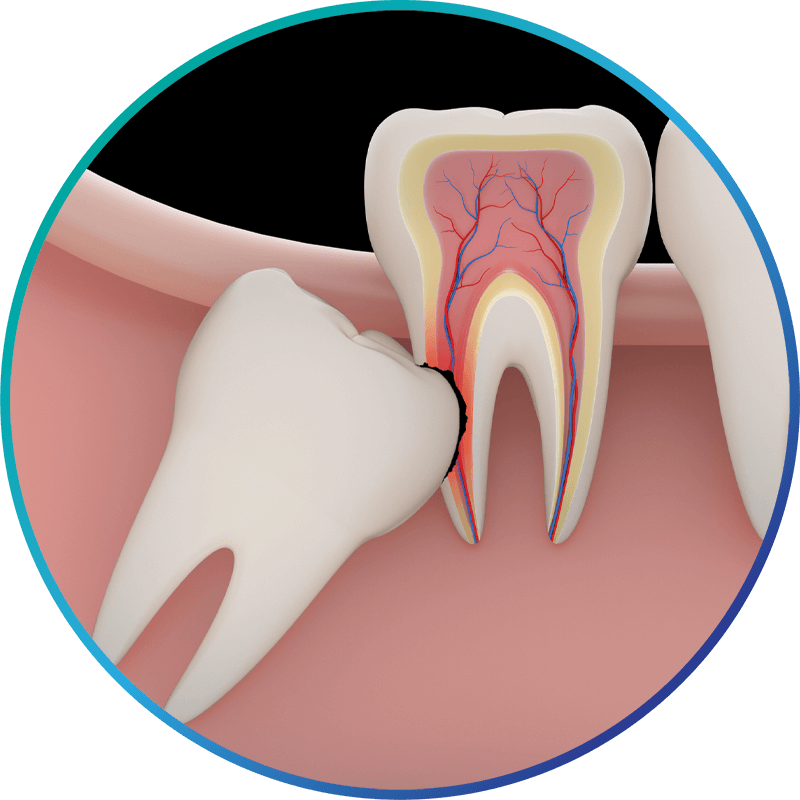

Impacted teeth are those which haven’t erupted fully through the gums. Impaction can occur with stubborn baby teeth, wisdom teeth, as well as permanent adult teeth.

Sometimes adult teeth are unable to erupt for various reasons: higher than the normal number of teeth are in the mouth, obstructive growths, and overcrowding from surrounding teeth are among the most common. Impacted teeth can cause a number of problems for the patient starting at an early age.

If these teeth are not able to come in fully, the child may have difficulty eating normally as well as suffer pain and tooth misalignment. In many other cases, symptoms may not appear until an x-ray presents the issue. We can offer a few options to resolve impacted teeth including working in collaboration with an orthodontist to guide the tooth to the proper placement. In the case of wisdom teeth, we often recommend extraction.

Third molars, commonly referred to as wisdom teeth, emerge during the late teenage years or early 20s and have the potential to cause a variety of oral health problems. Almost 90% of people have or have had at least one impacted wisdom tooth, which indicates that there isn’t sufficient space for the teeth to erupt into a normal position. Their location in the very back of the mouth makes them hard to clean, hence more prone to decay, infection, gum disease, pain, and even the development of cysts or tumors in the surrounding tissues. They can also throw neighboring healthy teeth out of alignment.

Oftentimes, wisdom teeth are located in close proximity to nerves, sinus cavities, and other teeth, so it’s important that you have a skilled expert remove the teeth if they become impacted. As board-certified oral surgeons with medical degrees, we’re exceptionally qualified to remove your wisdom teeth while maintaining your comfort and safety at all times. We are extraction specialists for all types of teeth and remove problematic wisdom teeth—a more complex procedure than standard extractions—every day in our offices.